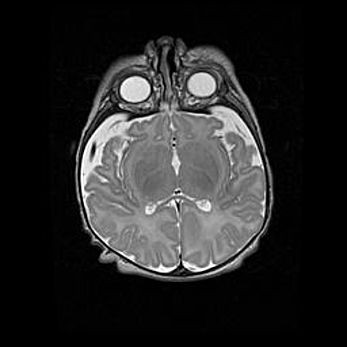

Церебральная ишемия II.

Возраст: 5 дней

Вес: 3400 г

Пол: женский

Окружность головы: 35 см

Срок гестации: 39 недель

Церебральная ишемия – это заболевание, характеризующееся недостаточностью (гипоксией) либо полным прекращением (аноксией) снабжения мозга кислородом по причине закупорки одного или нескольких сосудов. Это приводит к  что метаболическим расстройствам различной степени тяжести в тканях головного мозга, развитию коагуляционных некрозов и гибели нейронов.